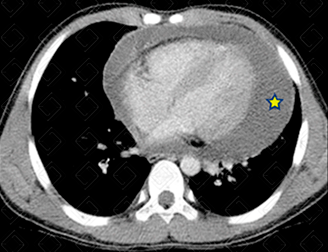

Texto alternativo para a imagem Figura 2. Créditos: Dra. Elazir Mota - Rio de Janeiro/RJ

Descrição das figuras 1 e 2: Tomografia computadorizada do tórax com contraste venoso. Volumoso derrame pericárdico (asteriscos). Paciento adulto jovem com febre e cansaço aos médios esforços. ADA do líquido positivo (+++). Diagnóstico de tuberculose confirmado.